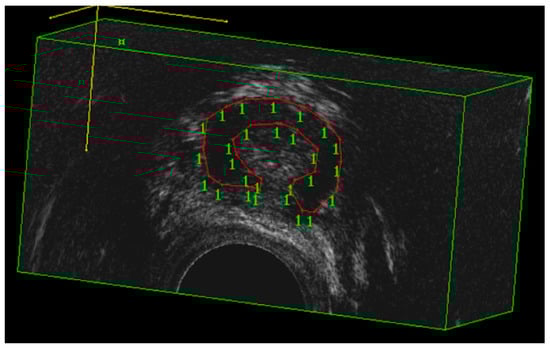

- Spelzini, F.; Cesana, M.C.; Verri, D.; Polizzi, S.; Frigerio, M.; Milani, R. Three-dimensional ultrasound assessment and middle term efficacy of a single-incision sling. Int. Urogynecol. J. 2013, 24, 1391–1397. [Google Scholar] [CrossRef]

- Hegde, A.; Rostaminia, G.; Quiroz, L.H.; Shobeiri, A.; Aguilar, V.C.; Davila, G.W. Are there age-related changes in the measurements of the urethral sphincter complex in nulliparous women? A three-dimensional ultrasound assessment. Int. Urogynecol. J. 2021, 32, 653–659. [Google Scholar] [CrossRef]

- Toozs-Hobson, P.; Khullar, V.; Cardozo, L. Three-dimensional ultrasound: A novel technique for investigating the urethral sphincter in the third trimester of pregnancy. Ultrasound Obstet. Gynecol. 2001, 17, 421–424. [Google Scholar] [CrossRef]

- Athanasiou, S.; Khullar, V.; Boos, K.; Salvatore, S.; Cardozo, L. Imaging the urethral sphincter with three-dimensional ultrasound. Obstet. Gynecol. 1999, 94, 295–301. [Google Scholar] [CrossRef]

- Digesu, G.A.; Robinson, D.; Cardozo, L.; Khullar, V. Three-dimensional ultrasound of the urethral sphincter predicts continence surgery outcome. Neurourol. Urodyn. 2009, 28, 90–94. [Google Scholar] [CrossRef]

| T0 Urethral rhabdosphincter volume (cm3) | 2.5 ± 0.9 | 2.5 ± 0.6 | 0.848 |

| URS volume (cm3) | 2.5 ± 0.9 | 2.9 ± 1.1 | <0.001 | 2.5 ± 0.6 | 2.6 ± 0.6 | 0.248 |

| T1 Urethral rhabdosphincter volume (cm3) | 2.9 ± 1.1 | 2.6 ± 0.6 | <0.001 |